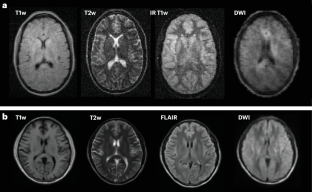

Deoni, S. C. et al. Accessible pediatric neuroimaging using a low field strength MRI scanner. Neuroimage 238, 118273 (2021).

Deoni, S. C. et al. Neuroimaging and verbal memory assessment in healthy aging adults using a portable low-field MRI scanner and a web-based platform: results from a proof-of-concept population-based cross-section study. Brain Struct. Funct. 228, 493–509 (2023).